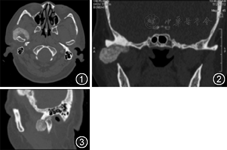

右颞下颌关节及颅底可见形态不规则结节状,T1稍长、T2不均匀信号影,间隙增宽,病变边缘光滑,与周围组织界限清晰,右侧翼内、外肌萎缩。增强扫描病变内可见不均质中等程度强化。提示:右颞下颌关节良性肿瘤(图4,图5,图6)。